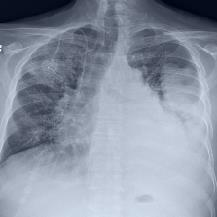

Thoracic disease detection from chest radiographs using deep learning methods has been an active area of research in the last decade. Most previous methods attempt to focus on the diseased organs of the image by identifying spatial regions responsible for significant contributions to the model's prediction. In contrast, expert radiologists first locate the prominent anatomical structures before determining if those regions are anomalous. Therefore, integrating anatomical knowledge within deep learning models could bring substantial improvement in automatic disease classification. This work proposes an anatomy-aware attention-based architecture named Anatomy X-Net, that prioritizes the spatial features guided by the pre-identified anatomy regions. We leverage a semi-supervised learning method using the JSRT dataset containing organ-level annotation to obtain the anatomical segmentation masks (for lungs and heart) for the NIH and CheXpert datasets. The proposed Anatomy X-Net uses the pre-trained DenseNet-121 as the backbone network with two corresponding structured modules, the Anatomy Aware Attention (AAA) and Probabilistic Weighted Average Pooling (PWAP), in a cohesive framework for anatomical attention learning. Our proposed method sets new state-of-the-art performance on the official NIH test set with an AUC score of 0.8439, proving the efficacy of utilizing the anatomy segmentation knowledge to improve the thoracic disease classification. Furthermore, the Anatomy X-Net yields an averaged AUC of 0.9020 on the Stanford CheXpert dataset, improving on existing methods that demonstrate the generalizability of the proposed framework.